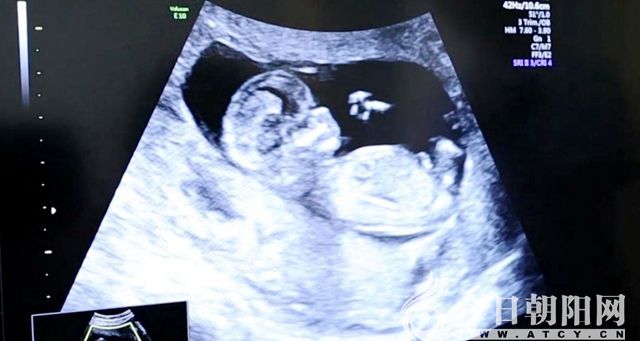

2018年11月,得知家門口的朝陽市中心醫(yī)院開展了“夫精人工授精技術(shù)”,致遠(yuǎn)夫婦便抱著試一試的態(tài)度前來就診。在此之前,夫婦兩人為了能夠生一個(gè)健康的寶寶,想盡了辦法,輾轉(zhuǎn)多家醫(yī)院進(jìn)行檢查、治療,結(jié)果都以失敗告終。通過一段時(shí)間的基礎(chǔ)治療,生殖醫(yī)學(xué)中心的醫(yī)生為女方實(shí)施了自然周期“夫精宮腔內(nèi)人工授精”。緊接著,好消息接踵而來:2019年1月初,致遠(yuǎn)夫婦來院檢查時(shí),“血清β—HCG”指標(biāo)顯示受孕成功;2月初到院復(fù)查時(shí),他們?cè)诔曈跋裣驴矗牐┑搅颂禾バ姆€(wěn)健而有力的波動(dòng)。